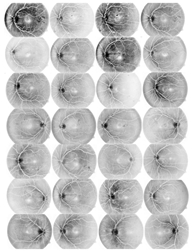

Figure 4.

Test images: (a) original images and (b) normalized images by using the averaging threshold optimization technique.